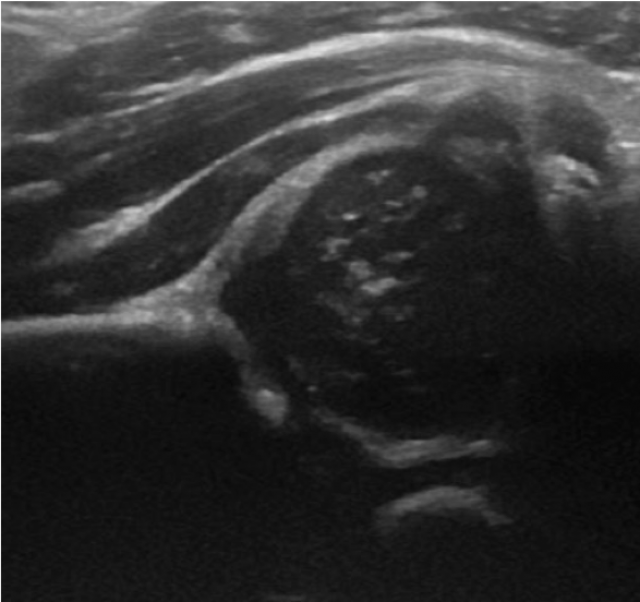

From www.columbiaradiology.org

Hip Dysplasia Ultrasound Introduced at ColumbiaDoctors Tarrytown Hip Dysplasia Is An Abnormal Growth Of The Bones Of The Hip Joint Developmental dysplasia of the hip (ddh) is a condition where the ball and socket joint of the hip does not properly form in babies and young children. It's sometimes called congenital dislocation of the hip,. The condition can cause misalignment, movement, and. Hip dysplasia is most common. Hip dysplasia occurs when the two bones that come together in the hip. Hip Dysplasia Is An Abnormal Growth Of The Bones Of The Hip Joint.